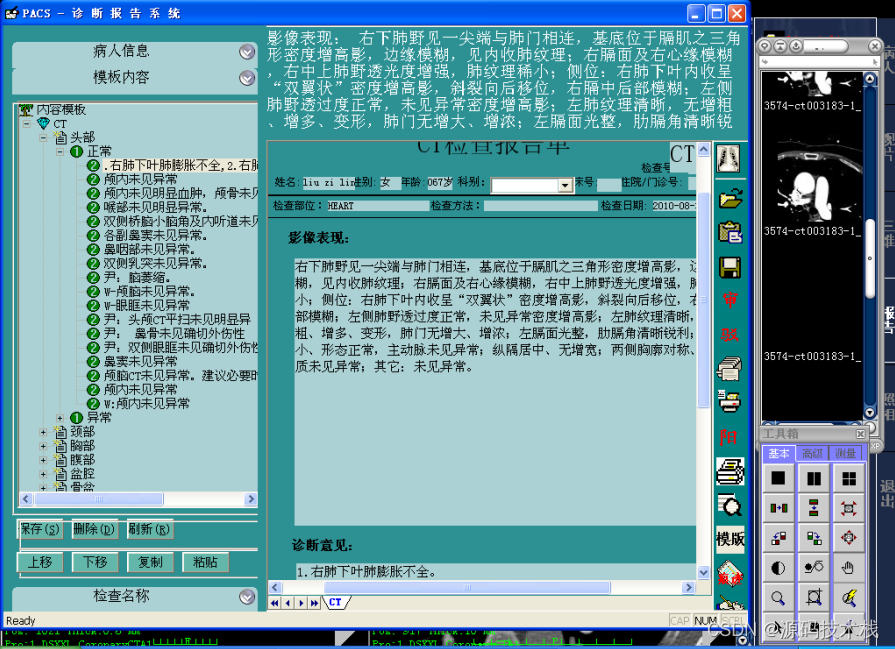

报告管理

系统支持支持报告编写界面按检查项目分类显示患者列表;

提供 图文报告的书写、修改、审核功能,支持权限管理;

支持记录报告修改痕迹;

支持多种类型的报告归档,如科研报告、典型病历等;

提供报告模板的编辑和修改功能;

提供报告打印功能,支持自定义打印格 式。

9. 影像诊断医生根据需要调阅检查影像。

10. 影像诊断医生对影像进行了修改或标注,则通知归档服务器更新信息并上传更新后的影像。

11. 影像诊断医生在PACS诊断工作站上书写检查报告。